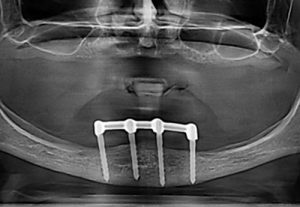

– "all on four"

"all on six" – implant solution concept for complete

tooth loss of upper or lower jaw supported by four or six

implants